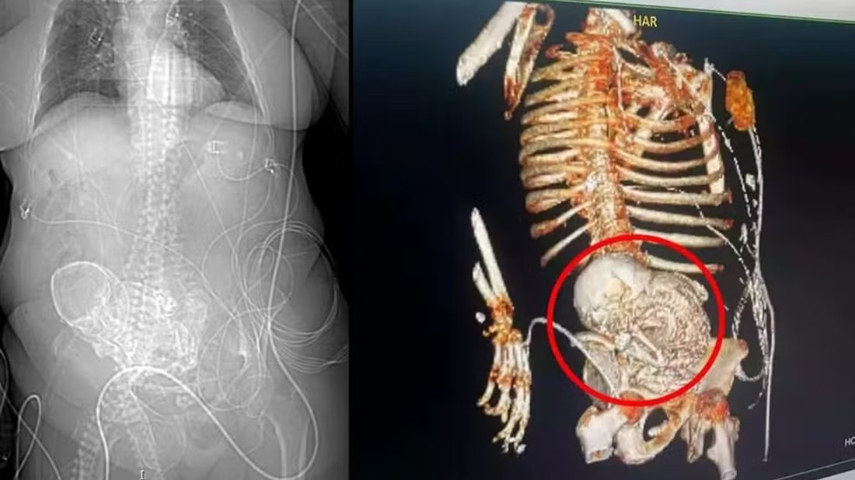

Idosa morreu após descobrir bebê calcificado em abdômen | Foto: Reprodução

Uma idosa de 81 anos foi surpreendida ao descobrir que carregava o que os médicos chamaram de um "bebê de pedra". Encaminhada para o Hospital Regional de Ponta Porã, na região sul de Mato Grosso do Sul, devido a dores abdominais, os profissionais de saúde suspeitaram que a mulher tinha um feto calcificado em seu abdômen há 56 anos, desde sua última gestação. Infelizmente, a idosa veio a falecer logo após passar por uma cirurgia para a remoção do feto.

ESTAVA COM INFECÇÃO GRAVE: Em 14 de março deste ano, a mulher foi admitida no Hospital Regional de Ponta Porã com uma infecção grave. No mesmo dia, uma tomografia revelou a presença do feto calcificado na região abdominal da idosa. Assim que se deparou com a situação, a equipe de obstetrícia da instituição foi acionada e realizou a cirurgia para retirada do feto. Após o procedimento, a idosa foi encaminhada para uma Unidade de Tratamento Intensivo (UTI) e morreu no dia 15 de março.

CASO RARÍSSIMO: O secretário de Saúde de Ponta Porã, Patrick Derzi, esclareceu que o nome da condição é litopedia. Derzi, que também é médico, explicou que o estado clínico da idosa representa um tipo raro de gravidez, que ocorre somente quando o feto de uma gestação abdominal não reconhecida morre e se calcifica dentro do corpo da mãe.